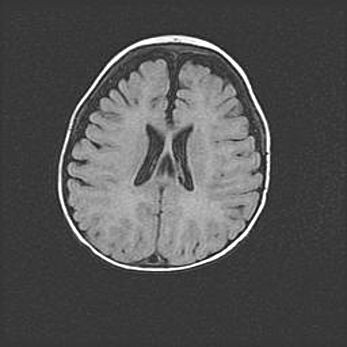

Множественные кисты обоих полушарий головного мозга, наибольшая из них в правой затылочной области. Ассиметричная атрофическая гидроцефалия.

Возраст: 7 месяцев

Вес: 5660 г

Пол: мужской

Окружность головы: 41,5 см

Срок гестации: 28-29 недель

Кисты головного мозга развиваются в результате многоочаговых некрозов вещества мозга и возникают вследствие перенесенной перинатальной инфекции, менингитов, энцефалитов, асфиксии, родовой травмы, расстройств мозгового кровообращения различного генеза. Образованию кист в веществе головного мозга плодов и новорожденных способствуют такие факторы, как высокое содержание в нем воды, недостаточная (или отсутствие) миелинизация и слабая астроглиальная реакция на повреждение.

Кисты могут сочетаться с гидроцефалией и другими поражениями головного мозга.